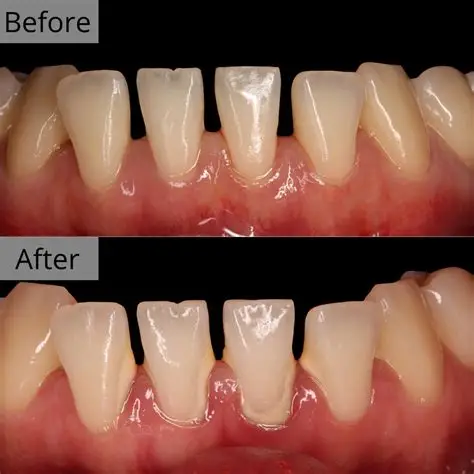

Subgingival Scaling (Deep Cleaning): The core treatment. Dentists use professional scalers (manual or ultrasonic) to reach deep into periodontal pockets, scraping off subgingival calculus and diseased tissues from the root surface.

Procedure Description: Local anesthesia may be administered for comfort. After scaling, the root surface becomes smooth, making it difficult for bacteria to reattach.